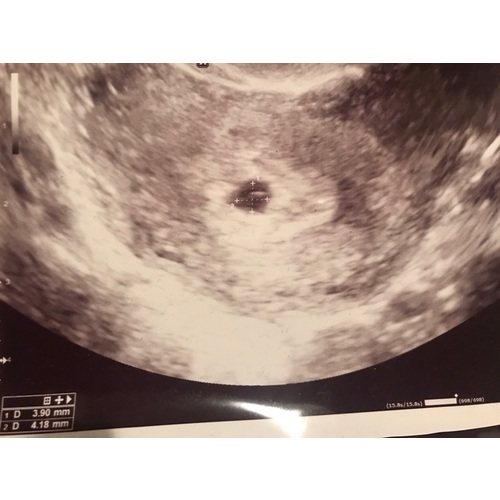

Ik heb ietsje eerder dan 6 weken een inwendige echo gehad in het ziekenhuis ivm eerdere miskramen. De gynaecoloog gaf aan dat ik ongeveer 5 weken en een beetje was. En het allermooiste was dat we het hartje zagen kloppen ❤️! En het vruchtje was ongeveer 3.66 mm. Maandag mag ik weer langskomen, dan ben ik exact twee weken verder.

Dankje! Deze was met 5+5, nu ik ze zo even bij heb gepakt zie ik dat ik meer heb gehad dan ik dacht 🙈 ( dit ivm eerdere missed abortion ) ook nog met 6+4, 9+3 en toen de 12 weken echo. Zelf met 15 weken geslachts bepalende echo laten maken en toevallig vandaag de 20 weken echo gehad. 🎀💗